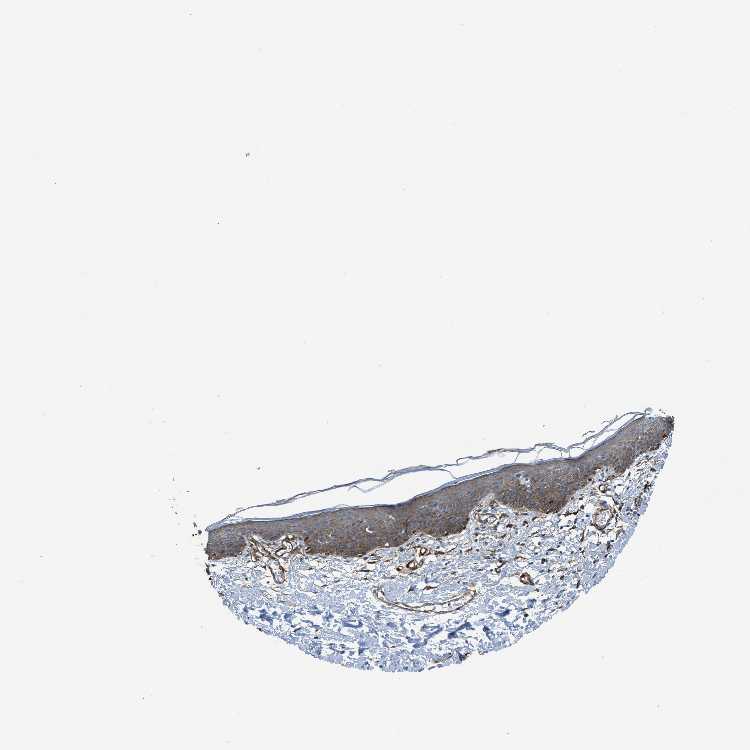

SKIN 2 - Antibody stainingi

Antibody staining in the annotated cell types in the current human tissue is reported as not detected, low, medium, or high, based on conventional immunohistochemistry profiling in selected tissues. This score is based on the combination of the staining intensity and fraction of stained cells.

Each image is clickable and will lead to virtual microscopy that enables deeper exploration of all samples and also displays staining intensity scores, fraction scores and subcellular localization as well as patient and tissue information for each sample.

Antibody HPA008066Antibody HPA017330Antibody CAB000006

Cells in basal layer --Not detected

Cells in corneal layer --Not detected

Cells in granular layer --Not detected

Cells in spinous layer --Not detected

Endothelial cells --High

Epidermal cells Not detectedMedium-

Extracellular matrix --Not detected

Fibrohistiocytic cells --Not detected

Langerhans cells --Not detected

Lymphocytes --Not detected

Melanocytes --Not detected

Sebaceous glands --Not detected

Vascular mural cells --High